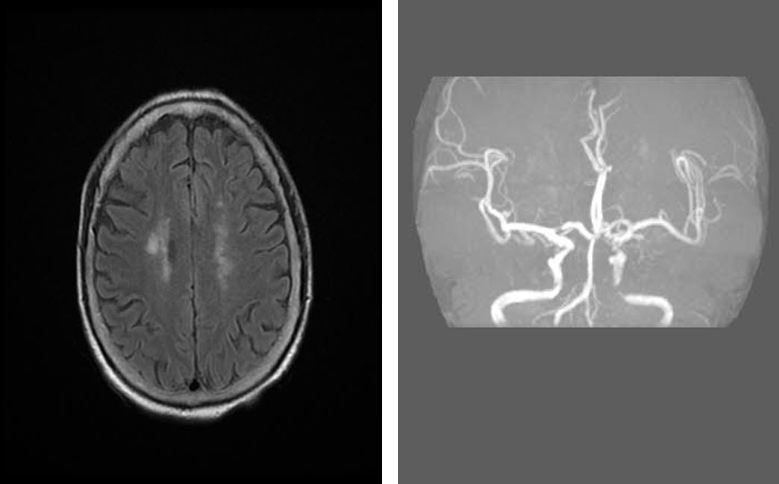

MRI(T2Flair)

导丝怎么扩重磅!NOVA颅内药物球扩支架湖北首例植入!_https://www.jmylbn.com_新闻资讯_第5张

MRA

重要影像结论:左侧大脑半球内侧多发陈旧性梗死灶,左侧颈内动脉C4段重度狭窄。